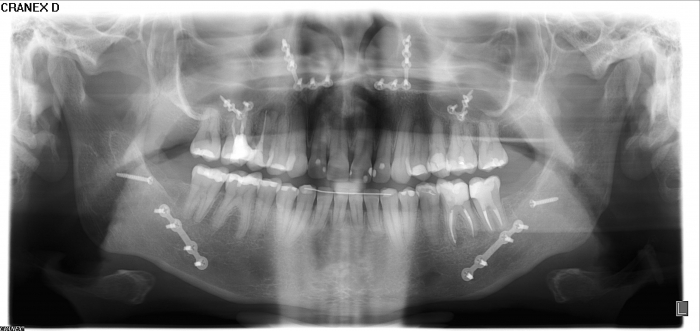

Rx Panorâmico Inicial

Rx panorâmico após a cirurgia